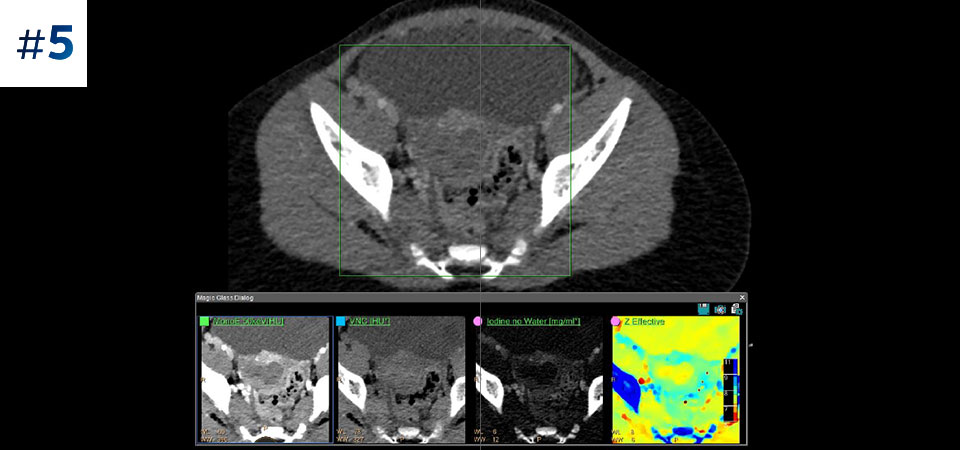

Chest for PE

Abdomen pelvis

Pediatric abdomen

Neck mass